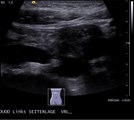

Duodenum nach Nahrungsaufnahme bei Wilkie-Syndrom: Widerstandsperistaltik

Das erweiterte Duodenum versucht vergeblich, Nahrung über die Kompressionsstelle, bestehend aus Arteria mesenterica superior und Aorta, zu transportieren. Dies ist charakteristisch für das Wilkie-Syndrom.